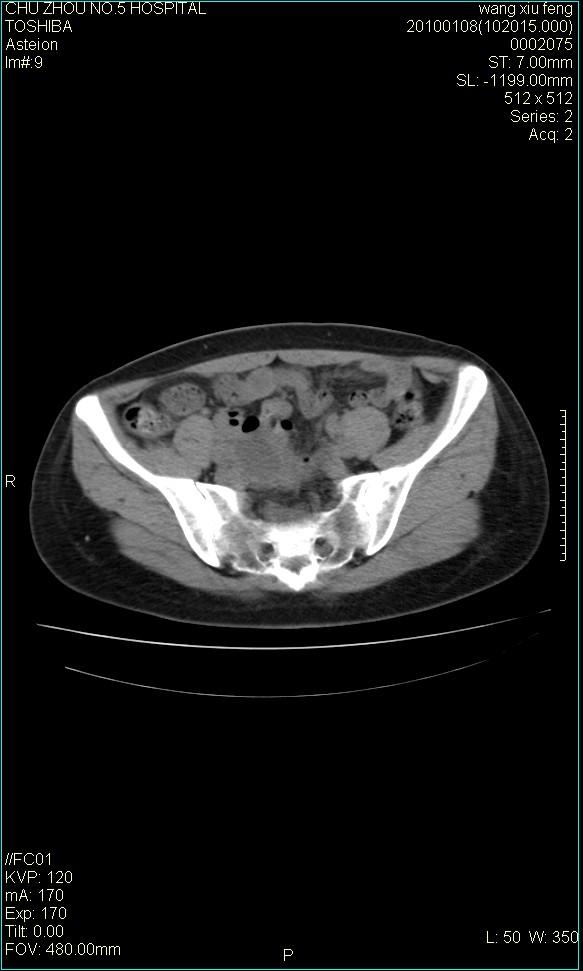

标题: CT24042:子宫右上方囊性包块,性质???? [打印本页]

标题: CT24042:子宫右上方囊性包块,性质????

f-41,左乳腺ca术后4年,b超示:子宫右上方囊性包块约5.5*3.4cm,前日行胸部ct平扫未见明显异常。